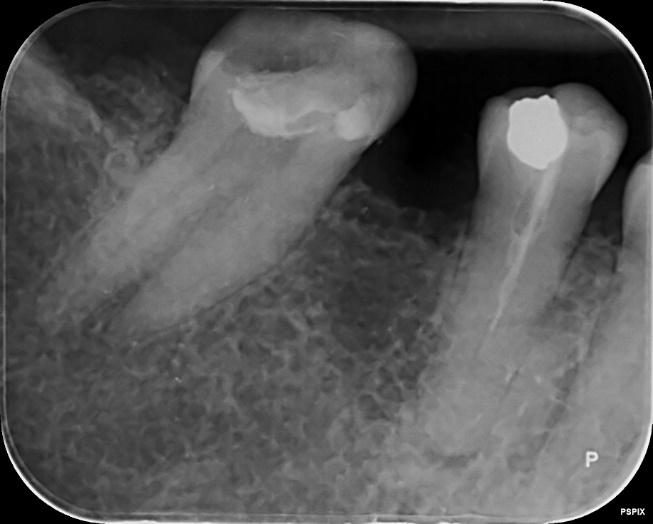

Lower Molar and premolar Primary root canal treatment